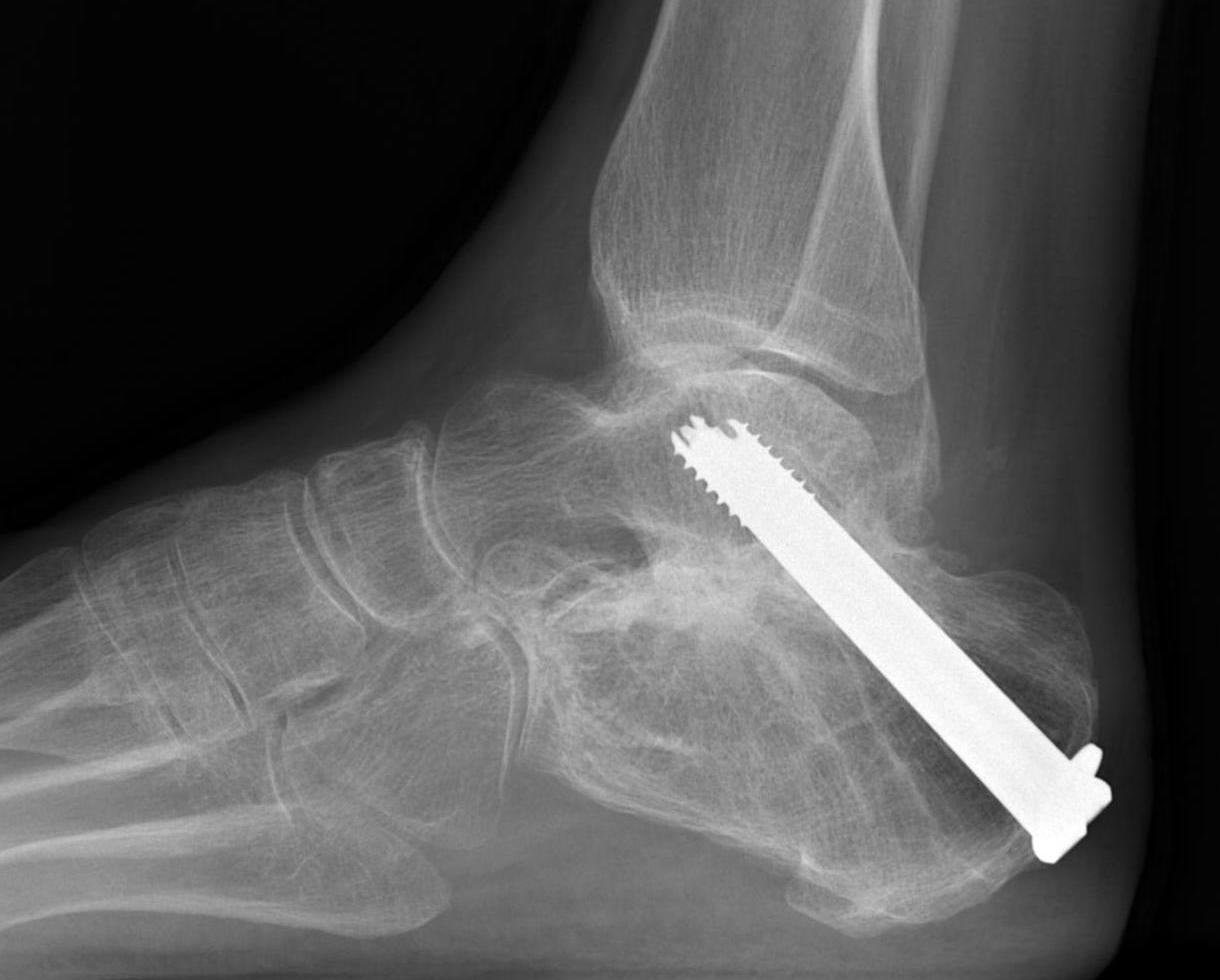

Fixation

- 6.5 mm/ 8.0 mm cannulated screw

- inferior calcaneum into body and neck of talus / talus to calcaneum